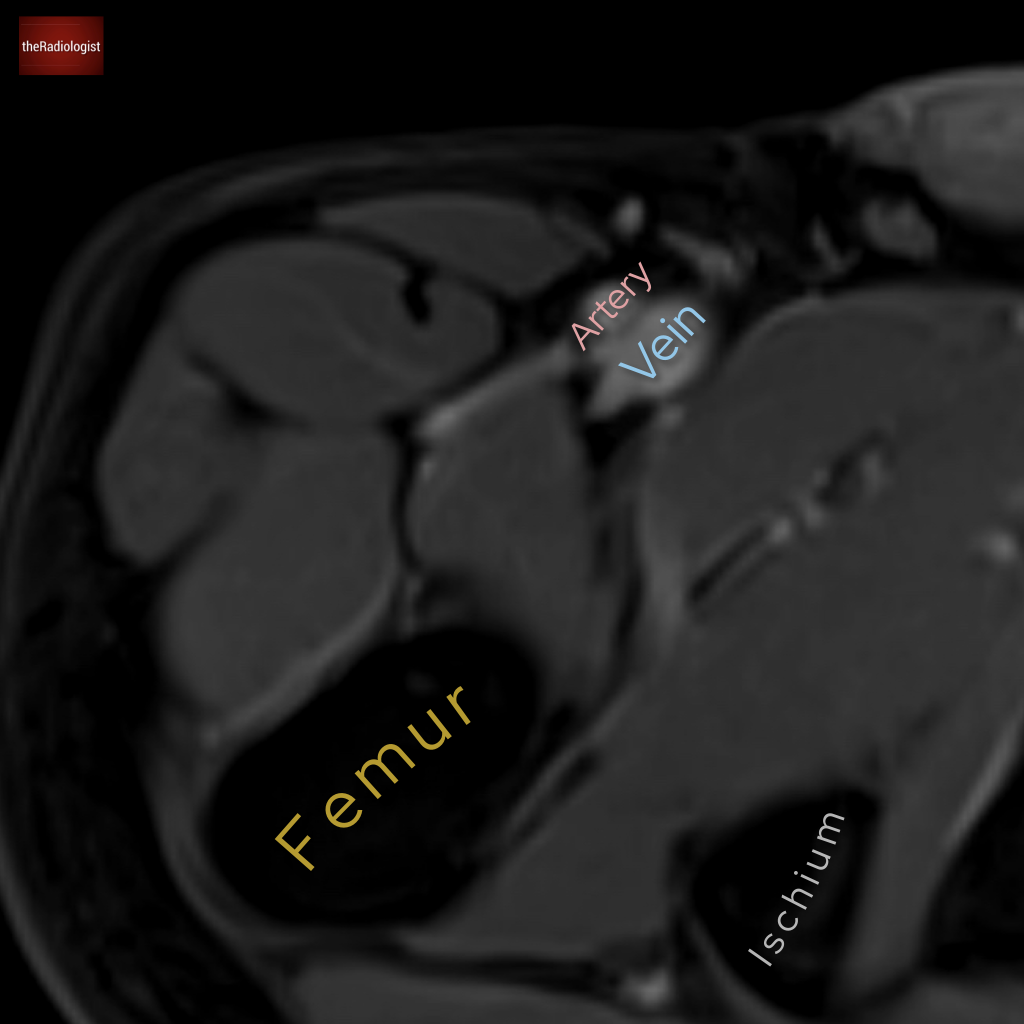

Another MRI, this time we’re going down to the pelvis. What is the arrow pointing at?

Choose from one of the following options: